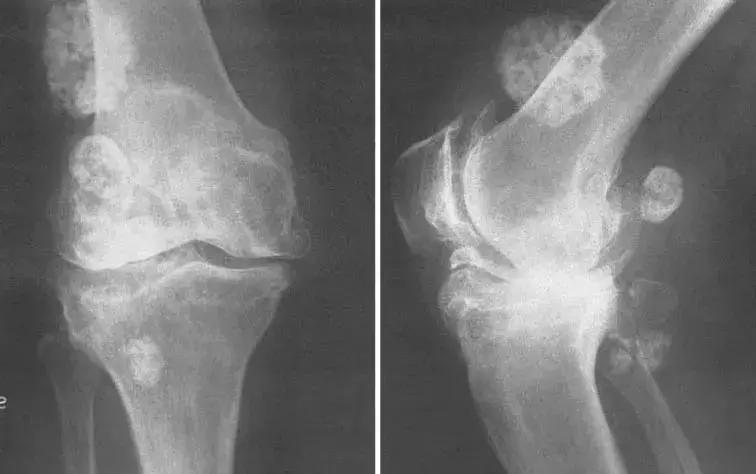

膝关节有严重的继发性骨关节炎